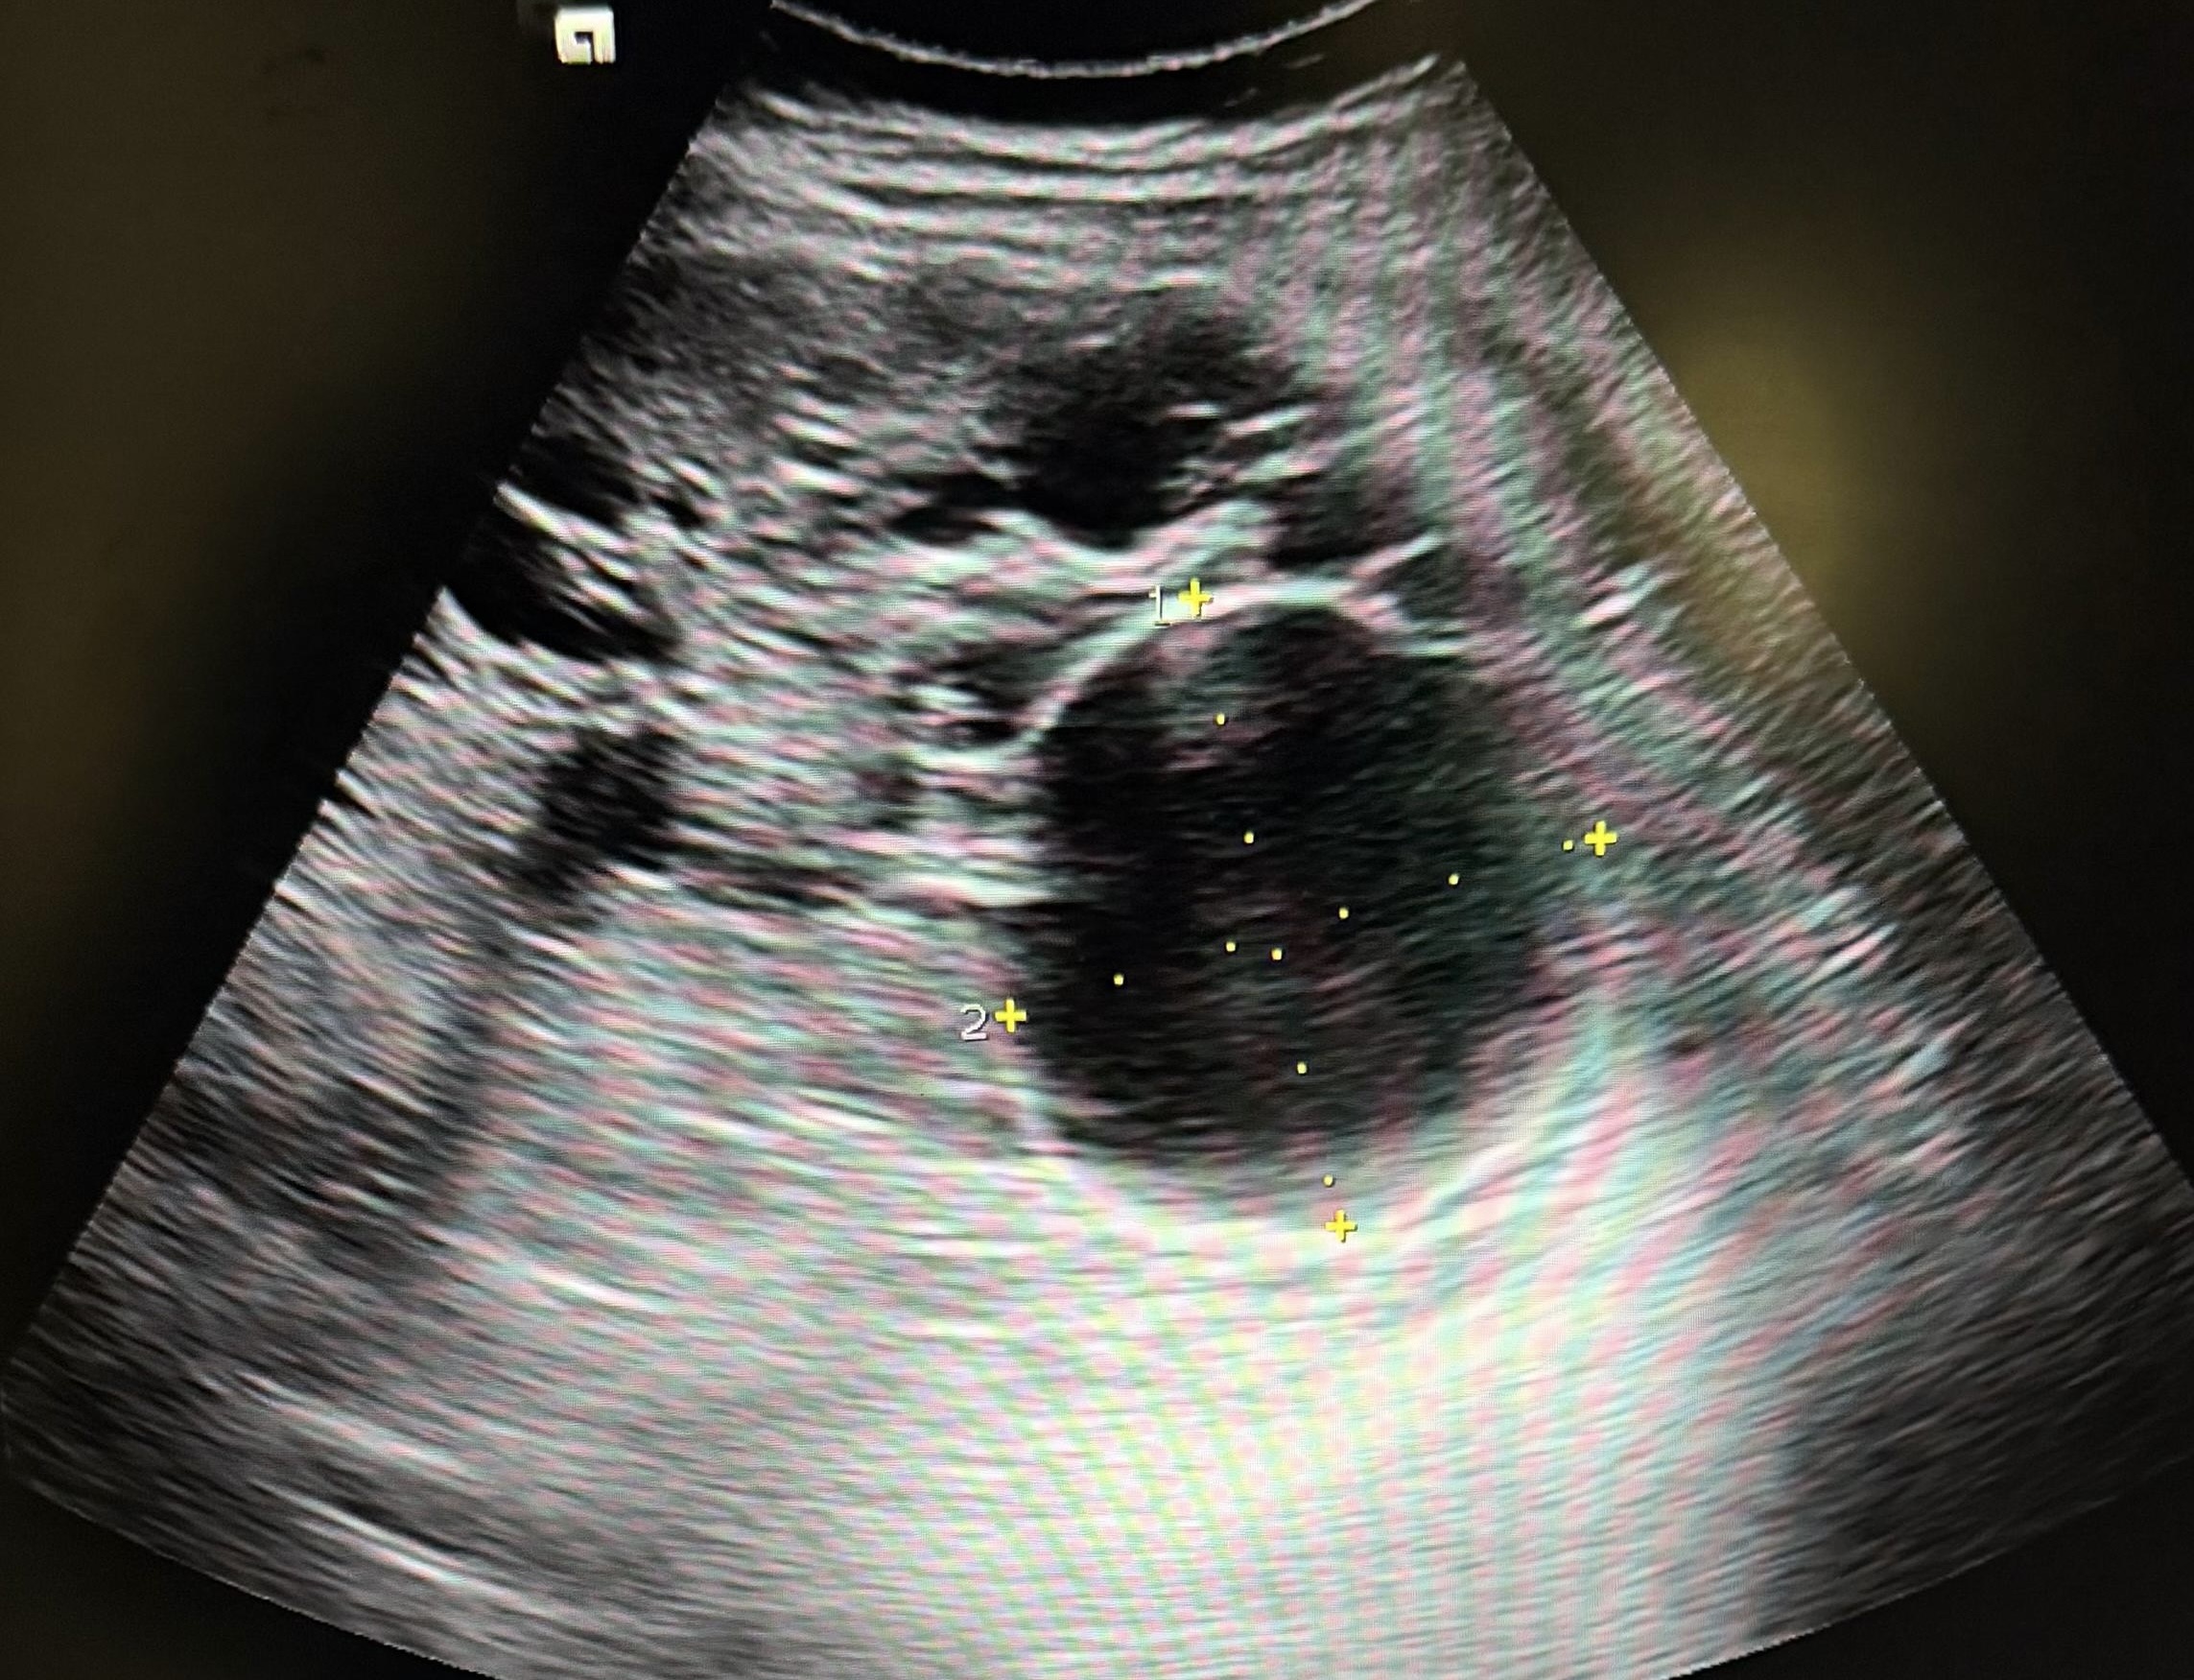

Hallazgos ecográficos

Imágenes quísticas hepáticas múltiples, sugerentes de ser quistes simples hepáticos; debiendo hacer despistaje de enfermedad de Caroli (hamartosis biliar intrahepática).